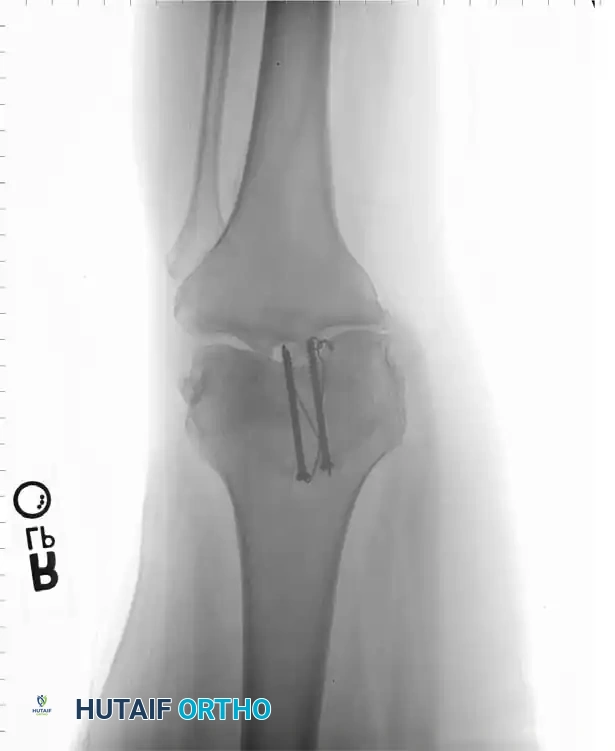

Cannulated Screw Fixation with Tension Band

Recent biomechanical advancements have popularized the use of cannulated screws combined with a tension band wire. Carpenter et al. demonstrated that transverse fractures fixed with a tension band wire passed through parallel cannulated screws failed at the highest load compared to K-wires or screws alone.

Berg described the fixation of displaced transverse fractures using a figure-of-eight wire passed through parallel cannulated compression screws. Advantages of this construct include:

* A low-profile construct that minimizes hardware irritation (a common complication of K-wires backing out).

* Enhanced interfragmentary compression provided by the lag screws.

* Superior biomechanical stability allowing for aggressive early restricted motion.

* Utility as a salvage method following the failure of traditional tension band wiring.

For transverse fractures with large, robust fragments, a tension band modified with cannulated screws is currently the preferred technique. If peripheral comminution is present, a supplemental circumferential cerclage wire can be added.